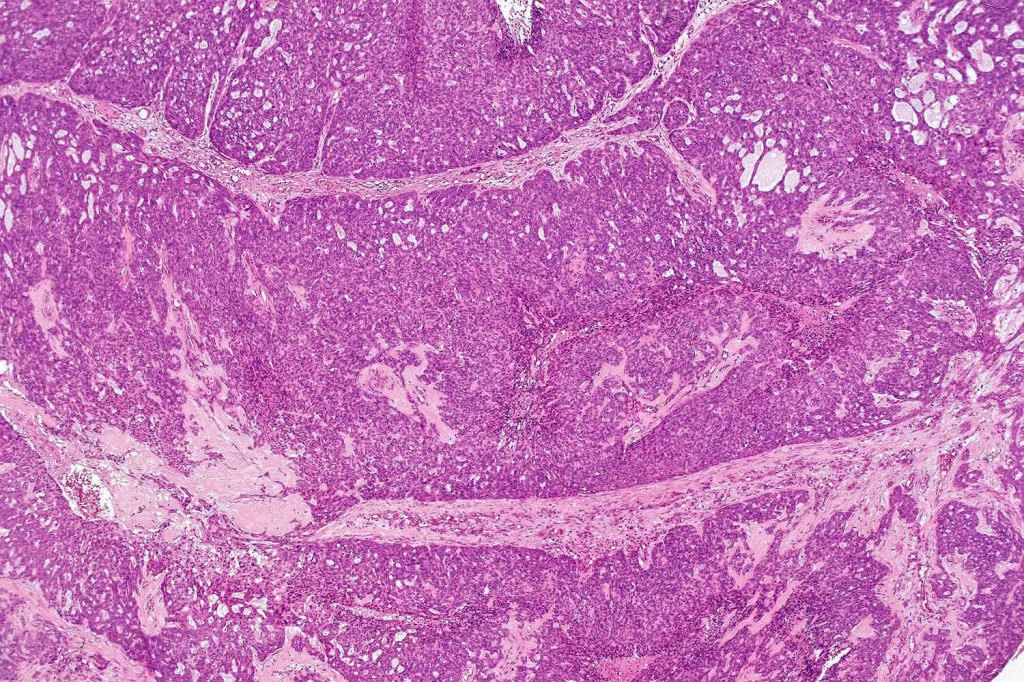

Carcinosarcoma

Cutaneous carcinosarcoma (metaplastic carcinoma, carcinoma with heterologous differentiation)

Histological features

•Osteoid

•Chondroid

•Smooth muscle

•MFH-like features with osteoclasts

•Neural differentiation